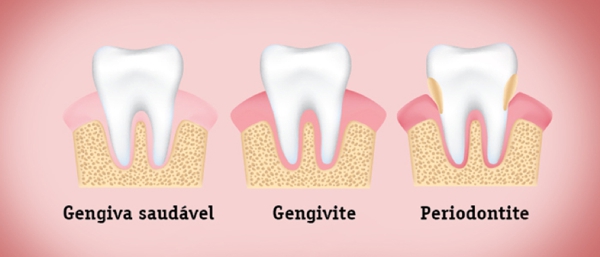

PERIODONTIA

A Periodontia é a especialização odontológica que trata as doenças do periodonto, ou seja, tecidos moles (gengiva), osso e ligamentos....

PERIODONTIA

A Periodontia é a especialização odontológica que trata as doenças do periodonto, ou seja, tecidos moles (gengiva), osso e ligamentos, estruturas de sustentam os dentes.

Mantendo a placa bacteriana sob controle, caso contrário, podemos ter tecidos inflamados e consequente perda dentária.

controle da placa bacteriana também deve ocorrer na fase de pré-instalação dos implantes e na fase de pós instalação da prótese definitiva, que são fatores chave para a longevidade dos implantes dentários.